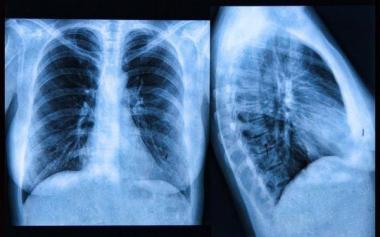

為啥肺癌查出多是晚期?其實(shí)4個(gè)呼吸道異常表現(xiàn)早已提醒你

肺是我們的身體與外界進(jìn)行能量交換的一個(gè)窗口,生命當(dāng)中每一次的呼吸吐納,都要通過(guò)肺來(lái)進(jìn)行。由于生活質(zhì)量和生活方式的改變,肺癌已經(jīng)成為全世界發(fā)病率和死亡率最高的...Read More